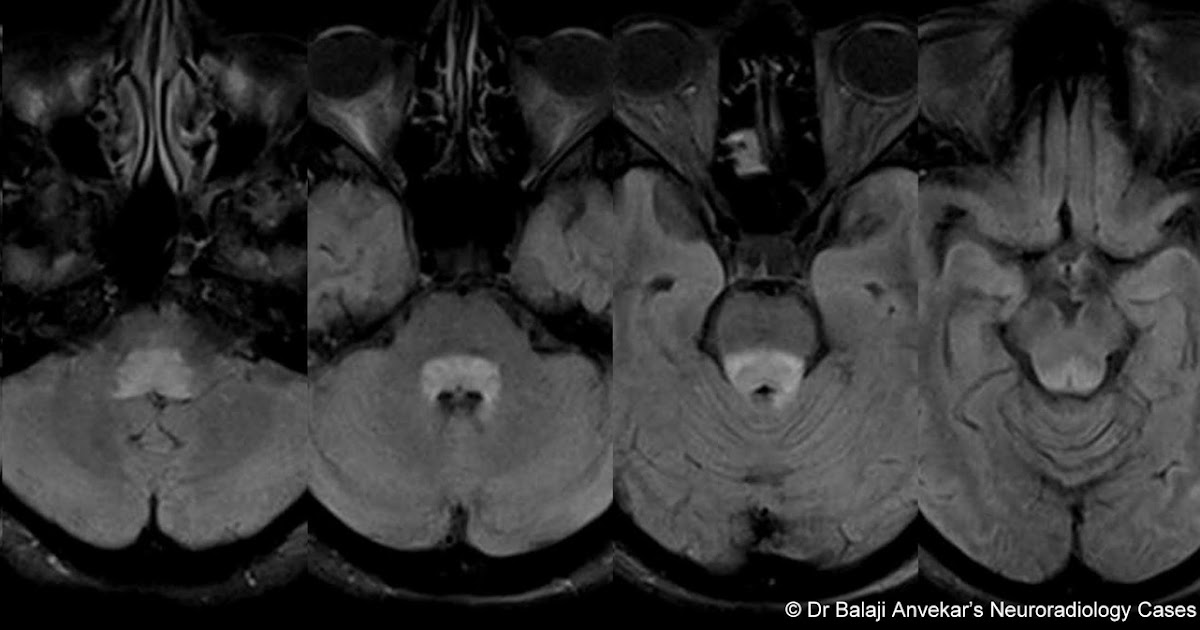

Dr Bahman Rasuli ◉ and Assoc Prof Frank Gaillard ◉ ◈ et al . Facial colliculus syndrome refers to a constellation of neurological signs due to a lesion at the facial colliculus, involving: abducens nerve (CN VI) nucleus facial nerve (CN VII) fibers at the genu

Facial Colliculus Syndrome Contributor: Christopher Kirkpatrick, MD The facial colliculus is an anatomic elevation on the floor of the 4th ventricle located medial to the sulcus limitance in the dorsal pons .

A male patient presented with horizontal diplopia and conjugate gaze palsy . Magnetic resonance imaging (MRI) revealed acute infarct in right facial colliculus which is an anatomical elevation on . . .

Facial colliculus pathology causes LMN type of facial palsy, diplopia and horizontal conjugate gaze palsy . The abducens nerve innervates the ipsilateral lateral rectus muscle and directly controls abduction in the ipsilateral eye .

The facial colliculus is an elevation on the floor of the fourth ventricle in the pons under which is located the abducens nucleus (cranial nerve VI) and the axons of the facial nerve nucleus (VII), which arc around the abducens nucleus . From: Netter's Atlas of Neuroscience (Third Edition), 2016

Facial colliculus syndrome usually results from a pontine glioma or a vascular accident • internal genu of CN VII • nucleus of CN VI underlie the facial colliculus .